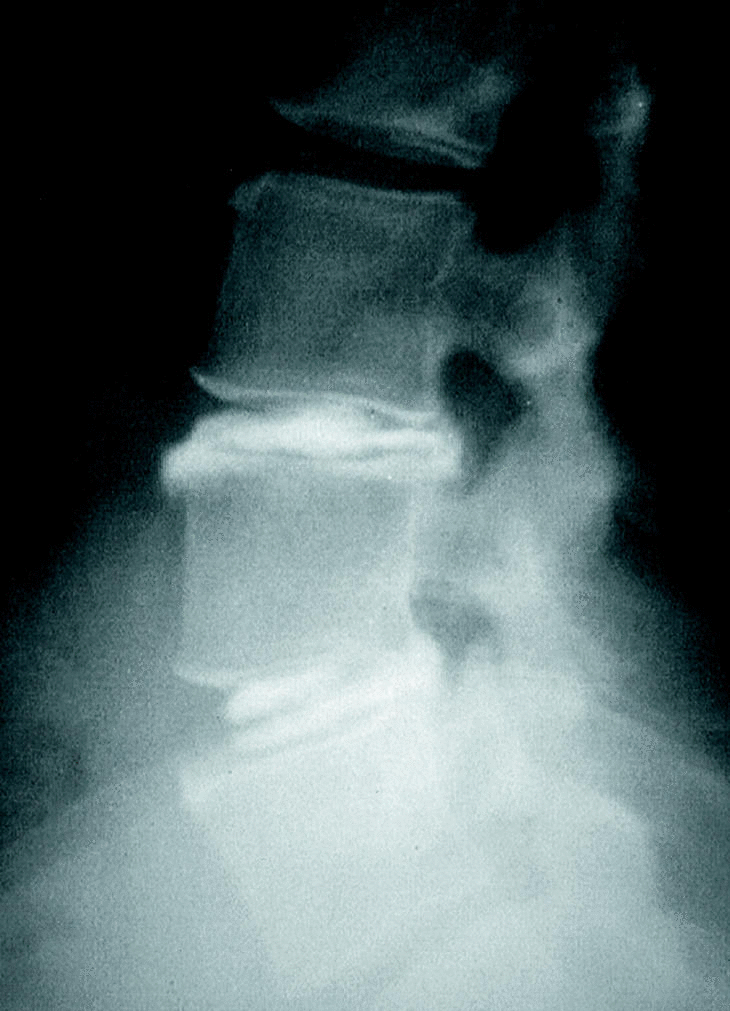

Once discos (18%) presentaron una morfología discal normal, 21 (34%) tenían abombamiento, 20 (33%) protusión y 9 (15%) extrusión. La presencia de extrusión mostró una sensibilidad del 18,4% pero una especificidad del 91% con un VPP del 78% (Tabla 4) (Fig. 2).

Figura 2. Extrusión discal L5-S1.

La disminución de la señal discal en T2 traduce la deshidratación del disco intervertebral y determina la existencia de un proceso degenerativo a nivel discal. Es el hallazgo más común en población asintomático y por ello el signo con menor capacidad para identificar los discos sintomáticos3. Distintos estudios han relacionado las alteraciones en la morfología discal con la degeneración discal y la presencia de síntomas asociados14,15. Millete et al estudiaron la correlación entre la morfología discal visualizada en la RM y la discografía en 135 discos de 45 pacientes con dolor lumbar crónico. En sus conclusiones, el abombamiento discal simétrico y la protusión discal no identifican los discos sintomáticos mejor que la disminución de altura discal, disminución de la señal en T2 o la presencia de zonas de alta intensidad en el annulus posterior14. En nuestro estudio, el abombamiento discal simétrico y la protusión discal presentaron un escaso valor predictivo positivo. Estos resultados quedan respaldados por la elevada prevalencia de estos signos en la población asintomática3. Los estudios de Stadnik et al hallaron prevalencias del 81% y del 33% respectivamente17. No sucede lo mismo con la extrusión discal, cuyo VPP en la identificación del disco sintomático es del 78% y cuya prevalencia en población asintomática es nula17.